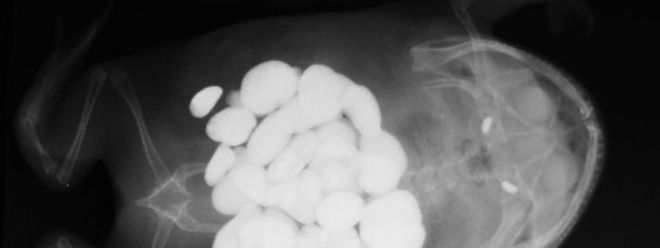

Tiere Wenn Die Dogge 43 5 Socken Frisst Augsburger Allgemeine

In Den Hund Gekommen Wenn Die Dogge 43 5 Socken Frisst